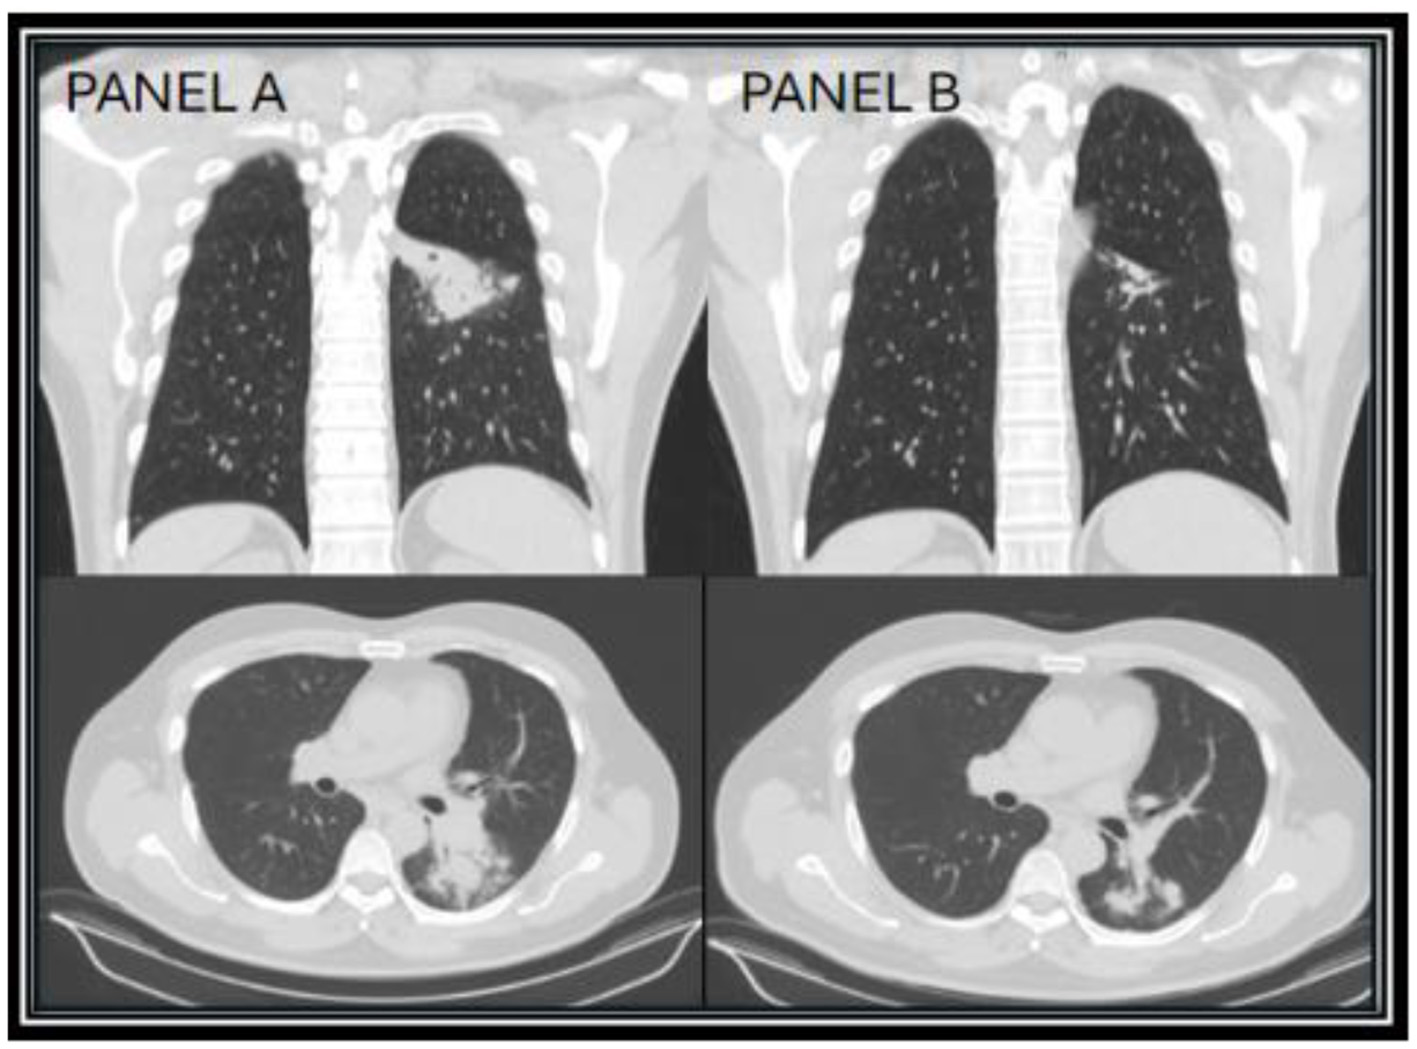

A 60-year-old male residing in Arizona with a history of PV on ruxolitinib therapy presented with a four-week history of productive cough with whitish sputum and intermittent fever. A chest computed tomography (CT) scan demonstrated a left lower lobe consolidation accompanied by satellite nodules and mediastinal lymphadenopathy (Figure 1A). He was initially treated with oseltamivir and levofloxacin by his primary care physician, without clinical improvement. Serologic testing returned positive for both Coccidioides IgM and IgG by immunoassay, with a complement fixation (CF) titer of 1:4. His diagnosis of pulmonary coccidioidomycosis was confirmed via a fungal sputum culture, and antifungal therapy with fluconazole was initiated; however, due to persistent symptoms after 2 weeks, he was transitioned to itraconazole. Itraconazole, a strong CYP3A4 inhibitor, is known to increase ruxolitinib blood levels. Given the potential for drug–drug interaction between itraconazole and ruxolitinib, the patient's hematologist reduced the patient's ruxolitinib dose by 50% from per oral (PO) 10 mg twice daily (BID) to PO 5 mg BID, with monthly monitoring of the patient's complete blood count, which remained within normal limits. The patient's serum itraconazole and hydroxyitraconazole levels remained within therapeutic range (>1 mcg/mL) throughout the patient's clinical course while on the antifungal, which was measured every 6 months.

Figure 1. CT chest images taken 1 month after diagnosis (year zero) of Coccidioides infection showing the superior left lower lobe infiltrate (A), and repeat CT chest taken 17 months on itraconazole showing improvement of the superior left lower lobe infiltrate (B).

After discussions with infectious disease and hematology regarding continued treatment of ruxolitinib in the setting of an active infection, the patient decided to continue ruxolitinib in conjunction with itraconazole, due to the patient's excellent disease control of his PV on ruxolitinib. On repeat chest CT done at 17 months of treatment, the patient's left lower lobe consolidation showed near resolution, with small residual fibrotic changes (Figure 1B). At the patient's follow up visit, he endorsed complete resolution of symptoms, with clinical improvement over 18 months. Due to presumed disease control, no elevation in CF titers (1:4), and proper IDSA recommended treatment length in immunocompromised patients, itraconazole was discontinued and the patient was counseled to call their provider with any relapse of symptoms (8). Additionally, 2 months later, the ruxolitinib dose was increased to PO 10 mg BID.